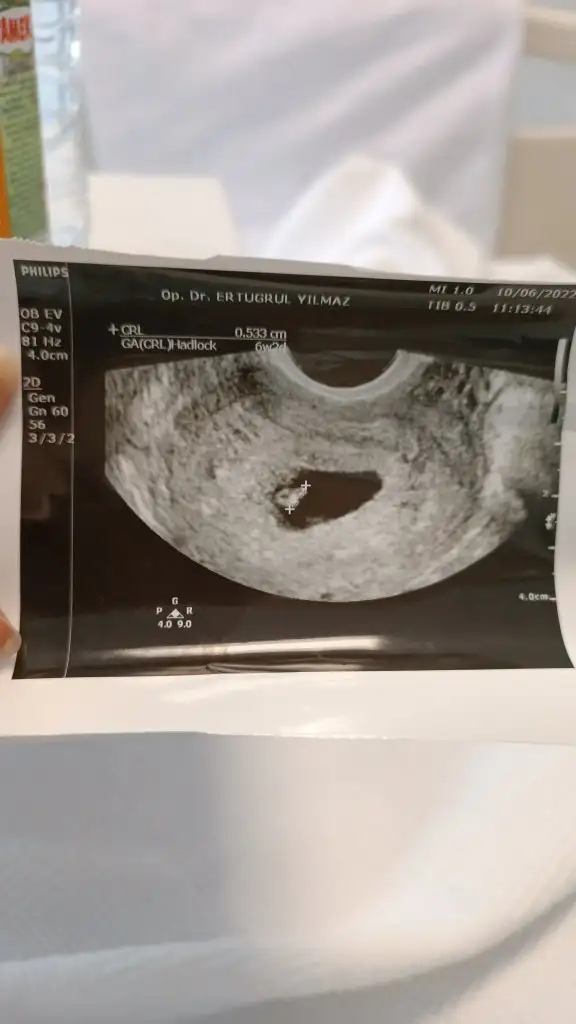

6 haftalık goruntum bu